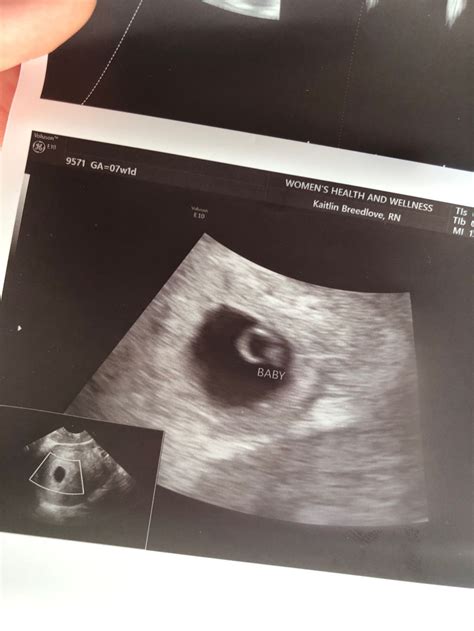

The 6 weeks ultrasound is typically performed transvaginally, as the embryo is still very small and an abdominal ultrasound may not provide clear images. This procedure involves inserting a probe into the vagina to get a closer view of the uterus and the developing embryo. The ultrasound technician will look for several key indicators of a healthy pregnancy at this stage.

• Gestational Sac: This is the first structure that can be seen on an ultrasound. It appears as a small, fluid-filled sac within the uterus.

• Yolk Sac: This structure is crucial for the early development of the embryo. It provides essential nutrients and helps in the formation of the early circulatory system.

• Embryo: At 6 weeks, the embryo itself is very small, often measuring around 2-4 millimeters in length. It will appear as a tiny, curved structure within the gestational sac.

• Fetal Pole: This is the earliest visible sign of the developing embryo. It appears as a thickened area within the yolk sac.

• Heartbeat: In some cases, a fetal heartbeat may be detected at this stage, although it is more commonly seen at 7 weeks. The heartbeat is a reassuring sign of a healthy pregnancy.

• Size and Shape: The gestational sac should be round and well-defined. The yolk sac should be visible within the sac, and the embryo should be clearly distinguishable.